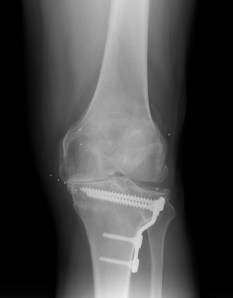

Los implantes de oro actúan a nivel de los tejidos blandos periarticulares. Los cambios funcionales y la desaparición del dolor son muy evidentes, en cambio no se observa cambio radiográfico alguno, al menos en el corto y mediano plazo. A continuación se observa un estudio de RX de un paciente con implantes de oro en ambas rodillas, con un marcado genu varo, y un cambio funcional y de mejora sintomática y de calidad de vida, inesperado incluso para el propio paciente.